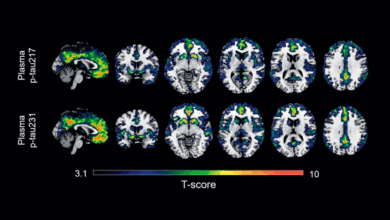

Redacción Xalapa.- La enfermedad de Alzheimer, es una enfermedad que va deteriorando la memoria, la capacidad de pensar y con el tiempo debilita la habilidad de poder realizar tareas simple, es por ello que la Comisión Federal para la Protección contra Riesgos Sanitarios (Cofepris) aprobó el registro sanitario de Lecanemab, un medicamento biotecnológico para el tratamiento de esta enfermedad en etapas tempranas.

“Este medicamento, está indicado para pacientes diagnosticados en etapa temprana de la enfermedad, en la cual pueden desenvolverse de manera independiente, pero manifiestan episodios de pérdida de memoria, como olvidar palabras familiares o la ubicación de objetos cotidianos”.